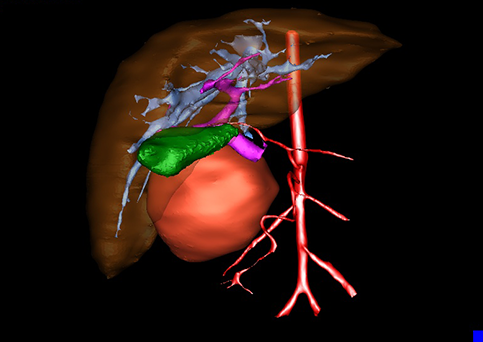

近年来由于数字医学的发展,基于可视化三维重建技术的计算机辅助手术系统极大推进了小儿肝脏肿瘤的精准手术的进步。可以立体透视肝脏解剖、精确掌握肝段的边界、精确测算肝段乃至任意血管所支配的功能体积、准确定位病灶及其与邻近血管的解剖关系,最终对不同手术方案进行比较、筛选和优化。因此,计算机辅助手术规划系统是实现精准肝切除的有力辅助工具,是未来数字外科、精准外科等21世纪外科新理念的重要技术支撑。

计算机辅助手术规划系统具有良好的操作可行性、计算准确性和三维显示效果,可半透明、交互式显示真实的肝内立体解剖关系和空间管道变异,准确计算肝内管道的直径、走行角度,两点间的垂直距离,和任意血管的支配或引流范围等传统二维影像无法获取的信息,有助于实施个体化手术,提高了手术的确定性、预见性和可控性。计算机辅助手术规划系统可直观显示预留肝脏的结构和功能,并可通过虚拟切割功能辅助术者对手术方案进行蹄选和优化,系统评估手术风险和制定对策,改变了部分二维规划的术式和切除范围,使部分二维规划认为不能切除的患者成功手术,提高了手术的根治性、安全性和病变的可切除性,更加符合精准肝脏外科的术前规划要求。详见第11章。

随着计算机技术及影像检查技术的不断发展,以精确的术前影像学和功能评估、精细的手术操作为核心的精准肝切除技术日益受到重视。基于数字医学的计算机辅助手术技术(computer-assisted surgery,CAS)则是实现肝脏精准手术操作的基础。计算机辅助手术系统(CAS)可将术前二维(two dimensional,2D)的CT/MRI影像数据进行三维(three dimensional,3D)重建,建立个体化的肝脏三维解剖模型,清晰显示肝脏内脉管系统的走行及解剖关系,还原病灶与其周围脉管结构的立体解剖构象,准确地对病变进行定位、定性和评估,制定合理、定量的手术方案,实施个体化的肝脏血管取舍分配方案及实施精准肝脏手术。一般认为CAS包括:创建虚拟的患者的图像;患者图像的分析与深度处理;诊断、手术前规划、手术步骤的模拟;术中实时导航。应用本技术后,由于可以更清晰地看出肿瘤的界限,特别是根据肝血管的显影,判断出肿瘤与门静脉及肝静脉的关系以在手术前较准确地估计出手术成功切除的可行性。以往部分根据普通强化CT判断无法手术的病例而被评估为可以成功切除并手术成功。